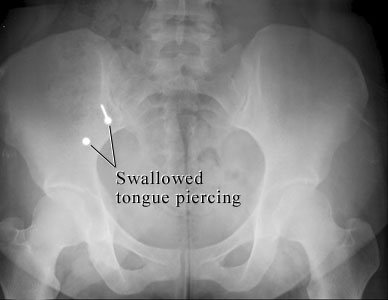

X-ray of swallowed mouth jewelry

Courtesy of Intermountain Medical Imaging, Boise, Idaho.

This X-ray of the belly shows two metal parts inside the bowel that were swallowed from a tongue piercing. The sharp stud could cause problems, while the blunt part is not likely to cause problems. Both parts are likely to pass in the stool.